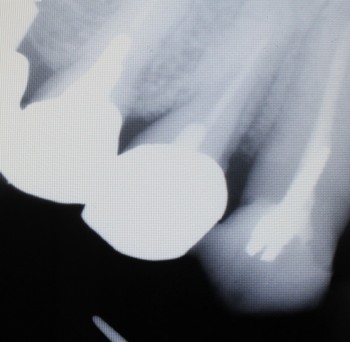

レントゲン像